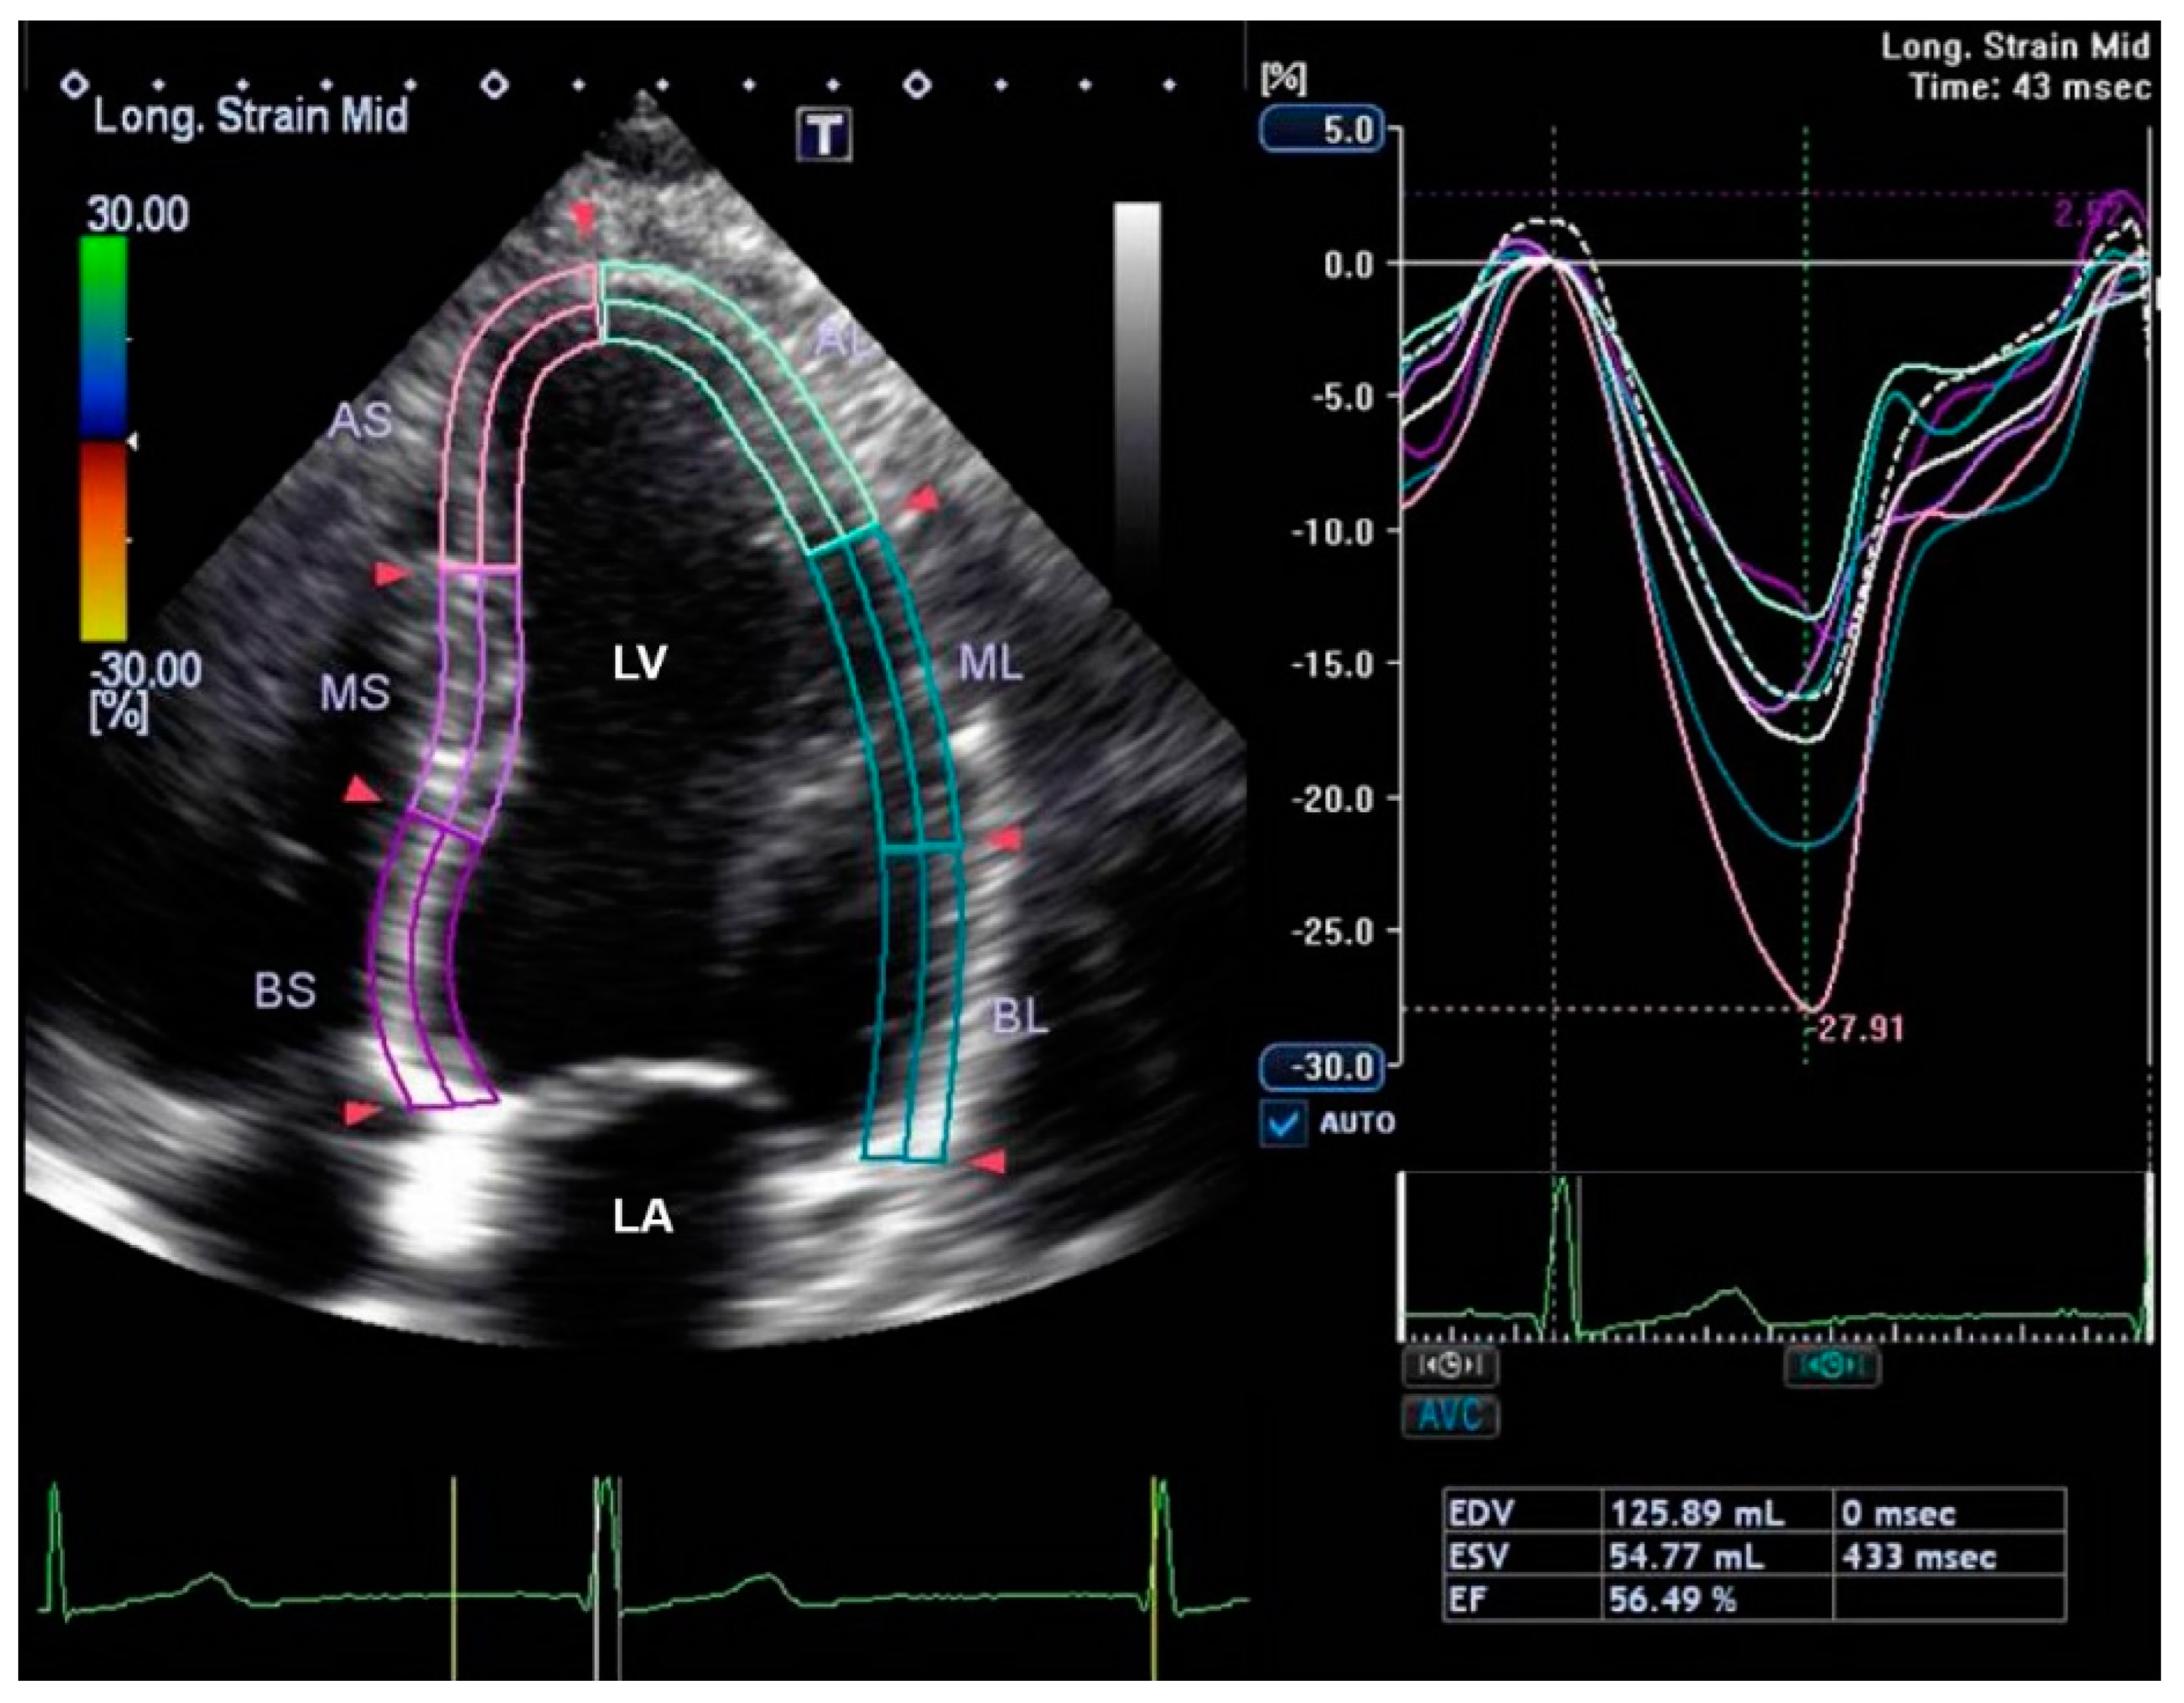

2.3. Maternal and Childhood Cardiovascular Assessment

| Speckle Tracking | |||

| Left-ventricular global longitudinal strain (%) | −23.2 (2.7) | −23.9 (2.5) | 0.240 |

| Left-ventricular-ejection fraction (%) | 62.6 (6.2) | 62.9 (5.0) | 0.853 |